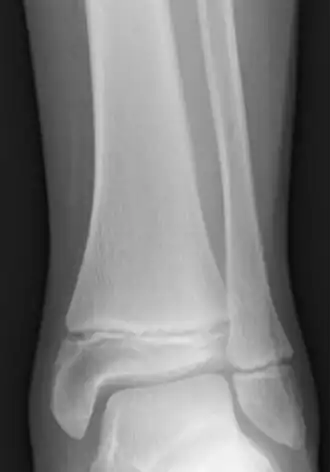

The epiphyseal plate, epiphysial plate, physis, or growth plate is a hyaline cartilage plate in the metaphysis at each end of a long bone. It is the part of a long bone where new bone growth takes place; that is, the whole bone is alive, with maintenance remodeling throughout its existing bone tissue, but the growth plate is the place where the long bone grows longer (adds length).

The plate is only found in children and adolescents; in adults, who have stopped growing, the plate is replaced by an epiphyseal line. This replacement is known as epiphyseal closure or growth plate fusion. Complete fusion can occur as early as 12 for girls (with the most common being 14–15 years for girls) and as early as 14 for boys (with the most common being 15–17 years for boys).[1][2][3][4][5]

Salter–Harris fractures are fractures involving epiphyseal plates and hence tend to interfere with growth, height or physiologic functions.[12]